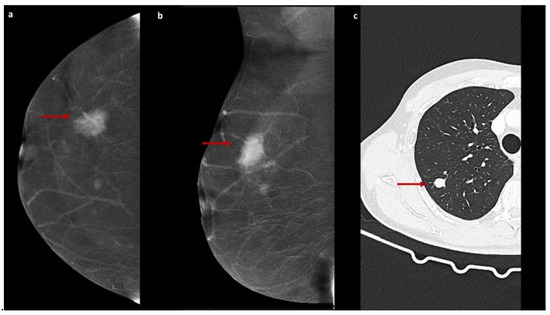

The field of radiology is undergoing a profound transformation spurred by the integration of artificial intelligence, advanced imaging techniques, and evolving clinical workflows. Specifically, contrast-enhanced mammography (CEM) has emerged as a promising tool for breast imaging, offering diagnostic performance comparable to that of MRI in certain scenarios. Meanwhile, artificial intelligence and radiomics are opening unprecedented opportunities for image analysis, prognostic modeling, and personalized medicine.

- Contrast-Enhanced Mammography: clinical applications, performance comparisons, technological innovations;